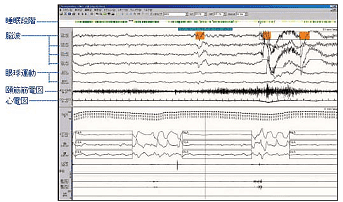

終夜睡眠ポリグラフィ(PSG)検査

-

- 当院医師による睡眠評価の例

- 終夜睡眠ポリグラフィ(PSG)検査表